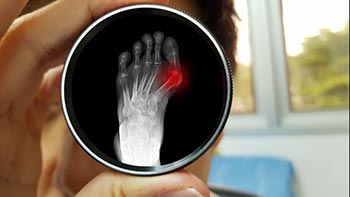

Minimally Invasive Bunion Surgery in Miami, FL

Bunion Surgery Miami Beach FL